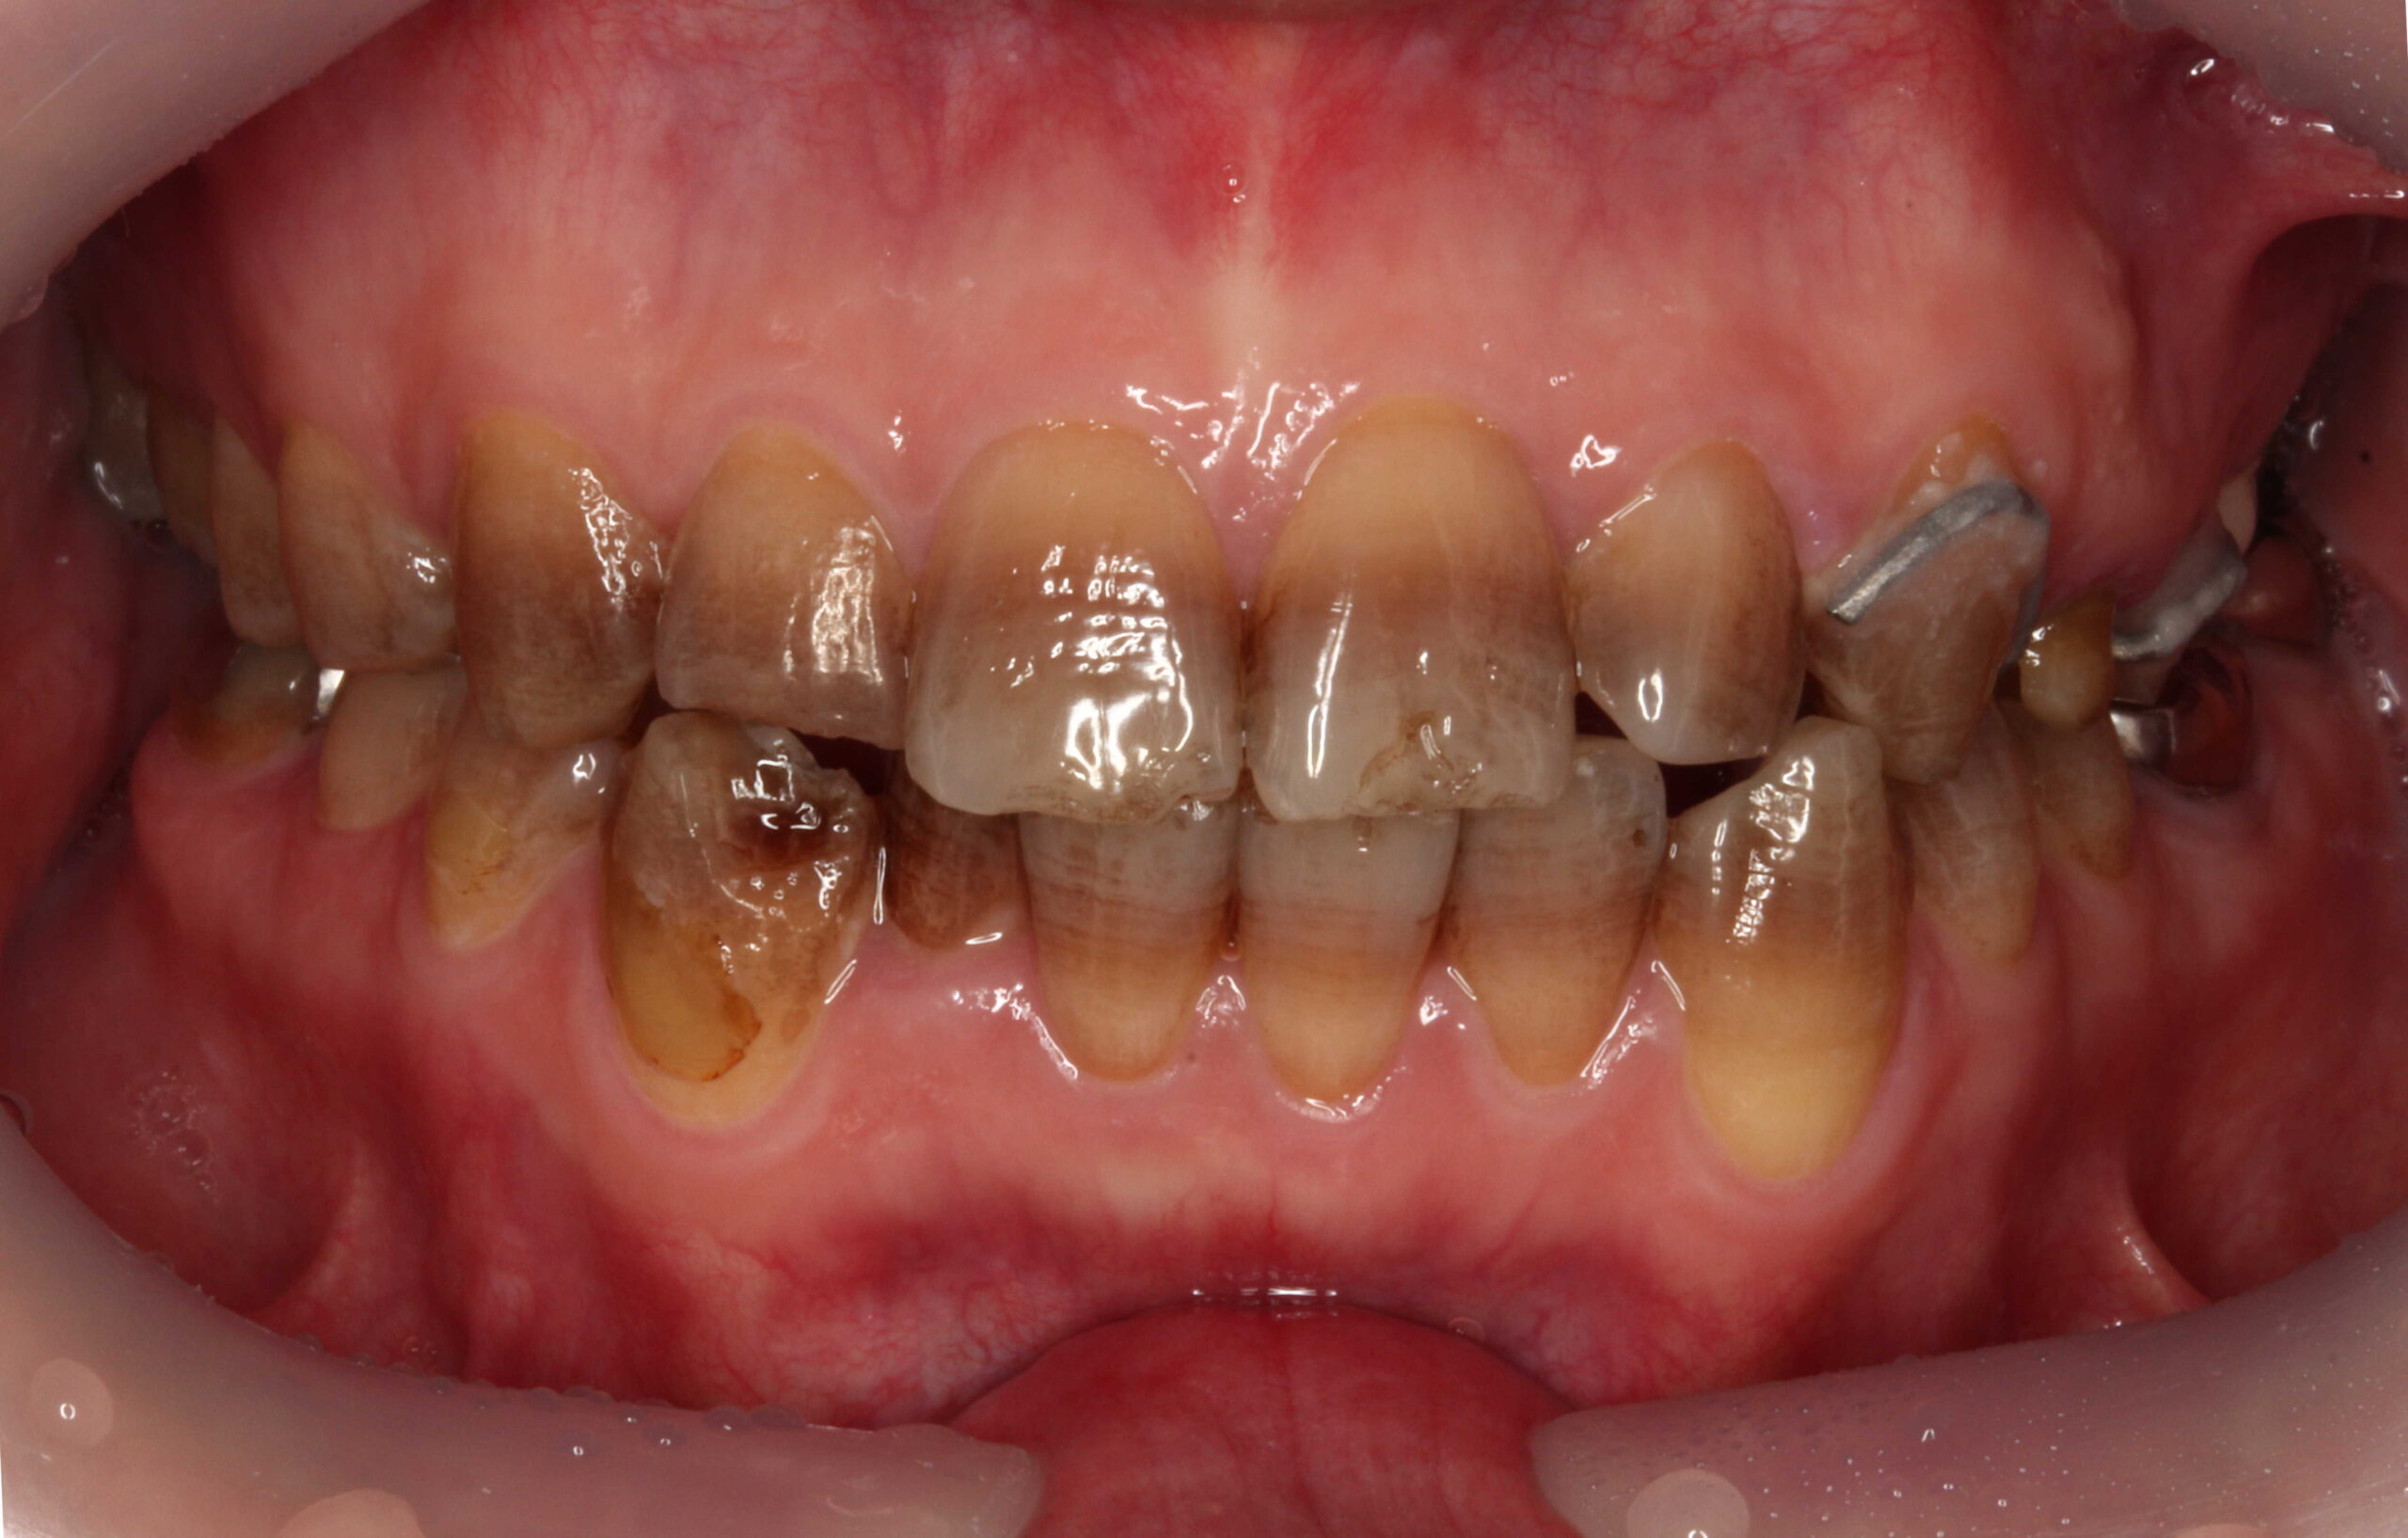

こちら、テトラサイクリン歯と失活歯と古いクラウンの症例となっております。

術前 削らないラミネートベニア4本

+クラウン2本

全体的にはホワイトニングを行っています。

テトラサイクリン歯 と 左上2や右下1などの失活歯 にもホワイトニング効果は出ています。

削らないラミネートベニアは極薄のセラミックベニアなので透明感があるので元の歯の色味が透けます。(透過性のないベニアも製作出来ますが、透明感がないので色味が白浮きして不自然になります。)

上の前歯(右上32と左上23) にも、削らないラミネートベニアの前にホワイトニングを行っています。

従来の方法であれば、上前歯6本をラミネートベニアやセラミッククラウンを行うために削って、セラミック材料を被せる方法で行っていました。